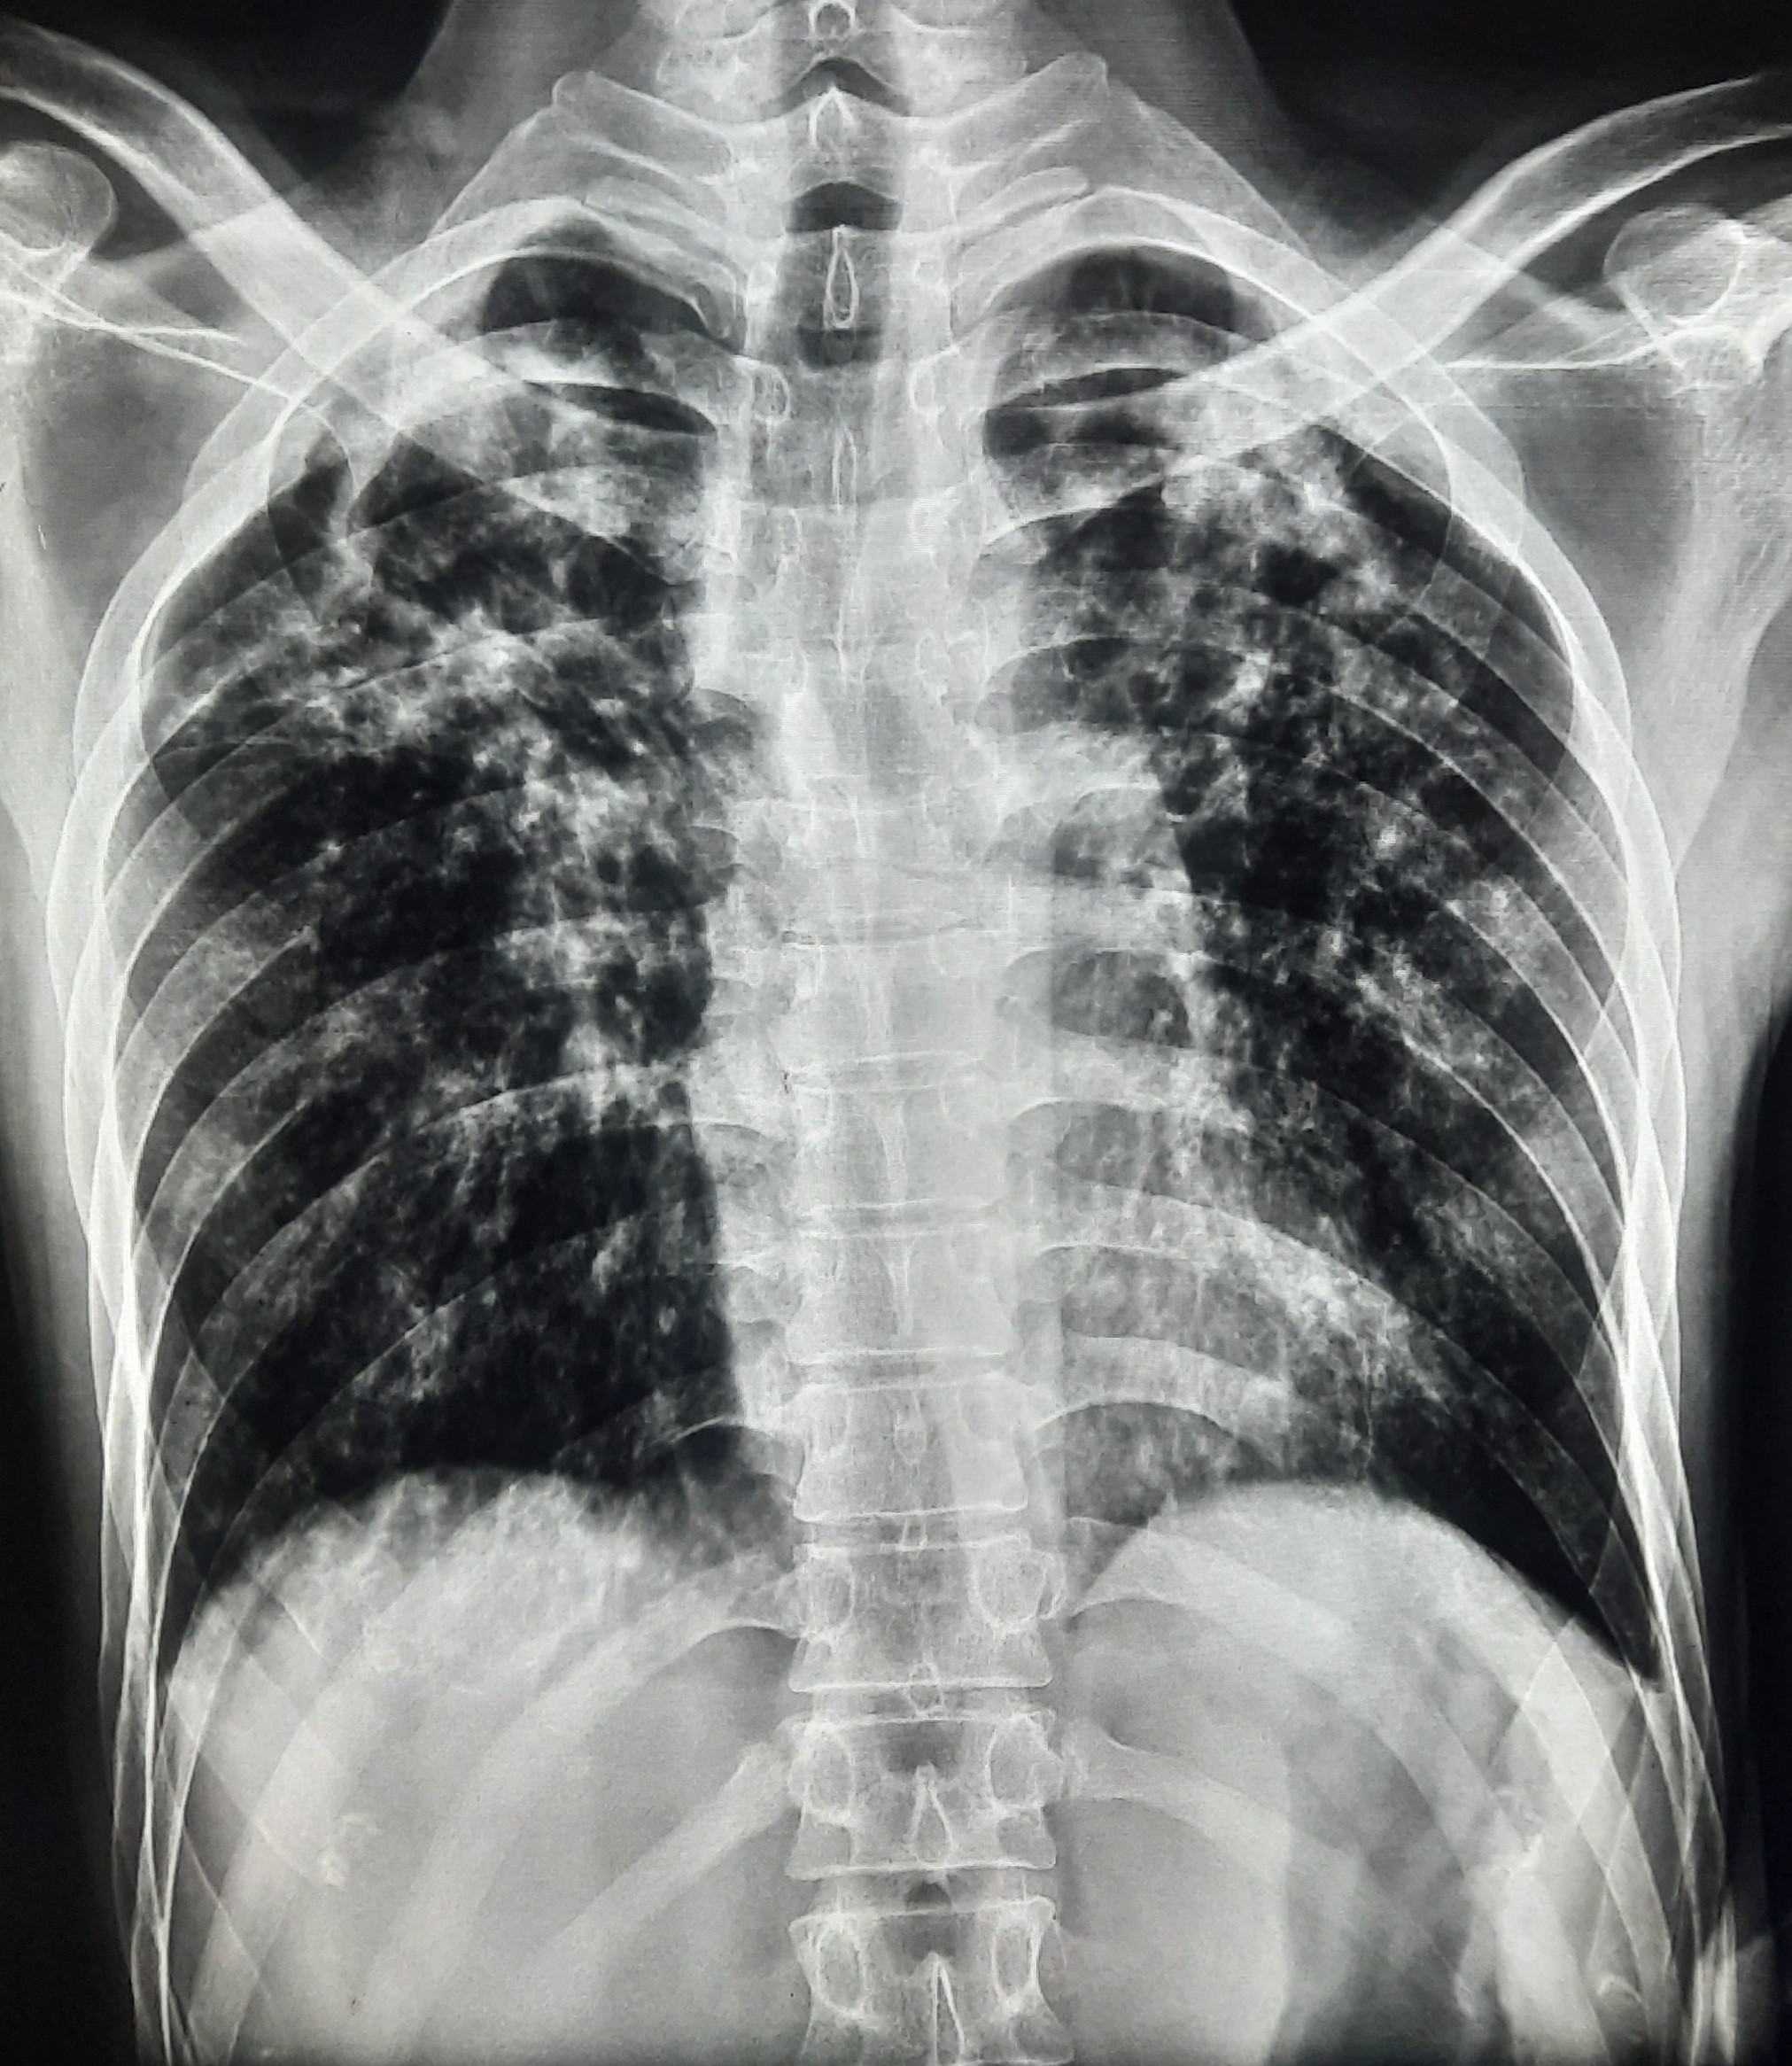

| 61 | IGGMC, Nagpur, Nagpur | P2 | 29-4411 | Roshan Ghushor | Consent taken on Paper | 32 Yrs. |

Provisional Diag : Post TB Sequelae With PTB Reactivation?

Final Diag : Pulmonary Tuberculosis |

TB Case (Confirmed) | Right Upper Zone Fibro cavitary Lesion Present, Right Mid Zone, Left Upper Zone, Mid Zone & Lower Zone Infiltration Present | Abnormality visible on x-ray |